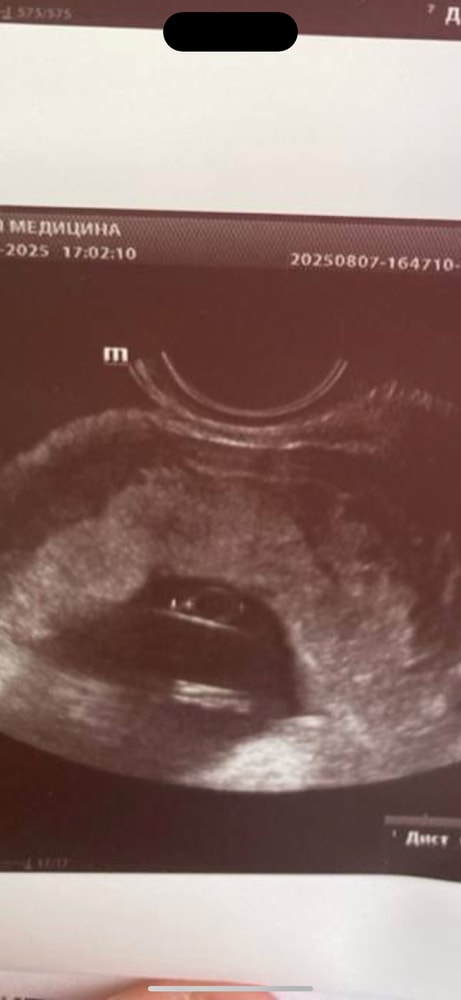

Анализы, скринингиУзистка намерила желточный мешочек 7 мм, и такая радостно «ну вот, хороший 7 мм». Я лежала с глазами по 5 рублей, даже не придумала что сказать. В результатах УЗИ написала норму по всему. Чего ждать? Остальные показатели в норме. ПЯ 7,4 см, КТР 3.8 см, я бы сказала, что КТР маловат. В целом по сроку проходит. Но смотрели через живот с полным мочевым.

Aurelia Man , больше чем уверена что она мерила с оболочкой, визуально у меня жм на последнем узи даже больше был чем на вашем фото 😅😅 не переживайте, я уверена что он нормального размера)